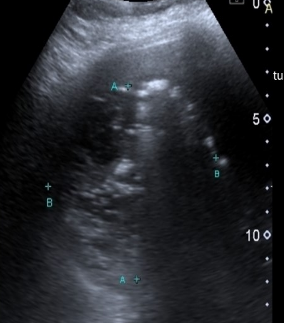

Identify this image.

Cirrhosis